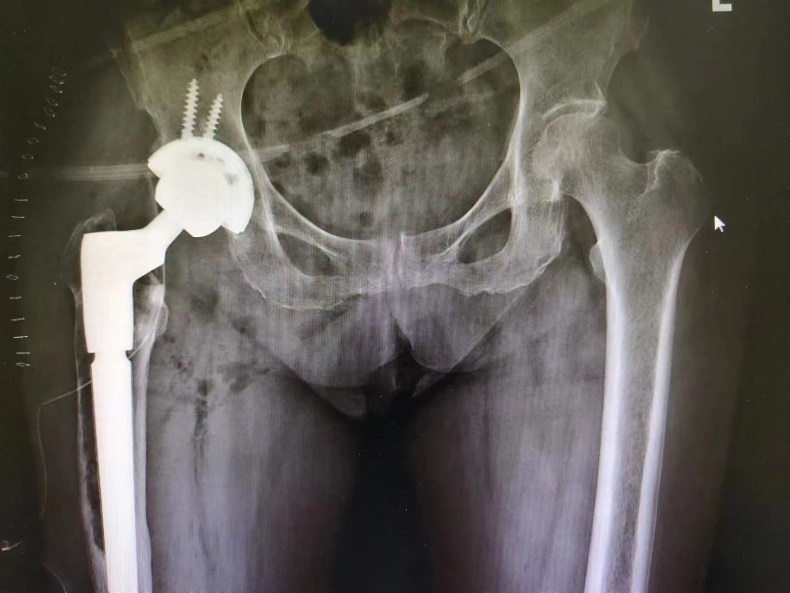

骨科副主任王建伟门诊查体并进行髋 DR 检查发现,患者右侧人工髋关节假体周围骨溶解严重,假体下沉松动。于是骨科团队考虑患者疼痛为人工髋关节置换术后假体松动所致,要想彻底治愈只能做翻修手术。

3 月 8 日,由骨科副主任王建伟主任医师主刀,李延明副主任医师、蔡文龙主治医师、杨志军住院总医师为助手,髋关节翻修手术历时 3 小时按照术前计划顺利完成。术后拍患肢 X 光片提示翻修假体型号、位置良好,完全纠正了术前患肢的短缩畸形。